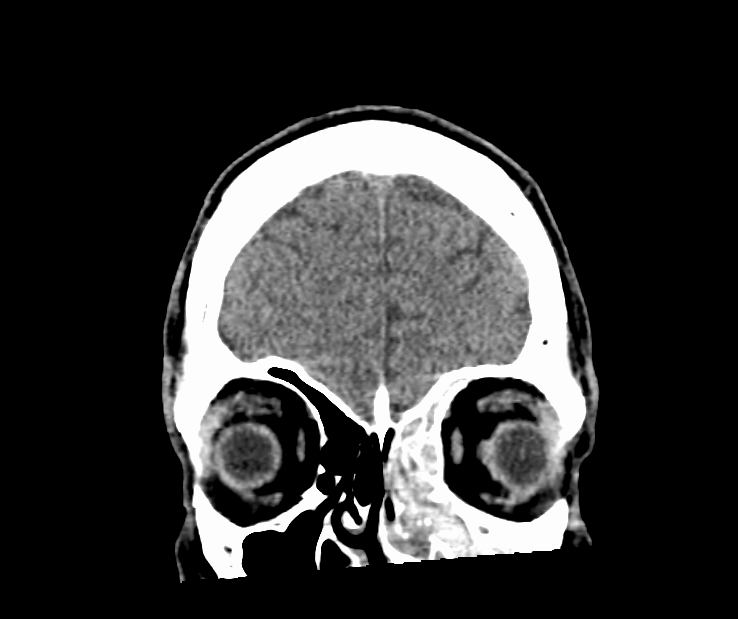

The patient is a 74 year-old African-American female with a history of hypertension, coronary artery disease status post drug-eluting stent ×1, former cigarette smoker, and iron deficiency anemia presenting with left-sided vision loss. Patient states that approximately two days ago  she woke up with painless peripheral vision loss of her left eye only. She describes it as darkness in the lateral portion of her left eye. She  reports that her vision returned to baseline throughout that day; only to return when she awoke the next morning. Since that time she endorses persistent vision loss in the left periphery. She denies blurry vision, eye pain, headaches, recent trauma, flashes, and floaters. Furthermore, she also denies dizziness, numbness weakness, dysarthria, dysphagia, fever, chills nausea, vomiting, chest pain, shortness of breath, and palpitations. She reports adherence to her antihypertensive and anti-platelet medications...